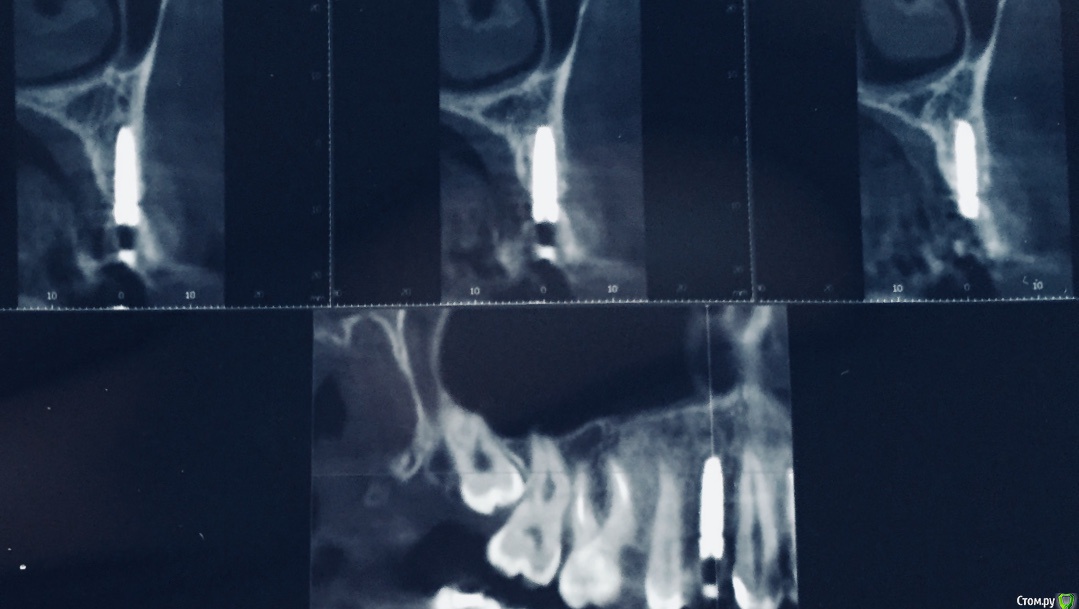

Mami Опубликовано 15 октября, 2018 Поделиться Опубликовано 15 октября, 2018 Уважаемые доктора, помогите оценить нормально ли стоит имплант. По моим ощущениям слишком близко со стороны щеки( чувствую когда провожу пальцем). Ссылка на комментарий

Bier Опубликовано 15 октября, 2018 Поделиться Опубликовано 15 октября, 2018 я бы сказал, что идеально. 4 Ссылка на комментарий